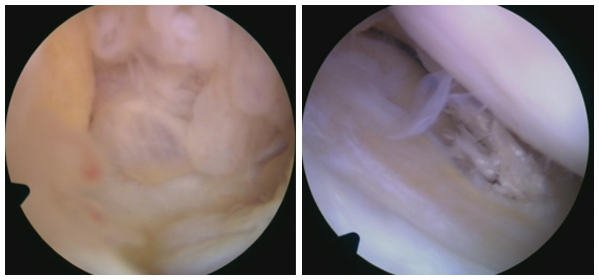

关节镜检查:微创手段,可直接观察关节内病变,同时兼具治疗功能。

- 手术治疗:中重度病变首选关节镜微创手术。通过2-3个直径0.5-1厘米的小切口,置入关节镜和器械,切除囊肿并根据半月板裂伤情况选择缝合修复或部分切除。术后需分阶段进行康复训练,逐步恢复关节功能。关节镜手术是一种微创技术,将带有摄像头和操作器械的关节镜置入关节内。摄像头实时传输关节内图像,医生通过监视器观察病变位置和程度,精准完成手术操作。